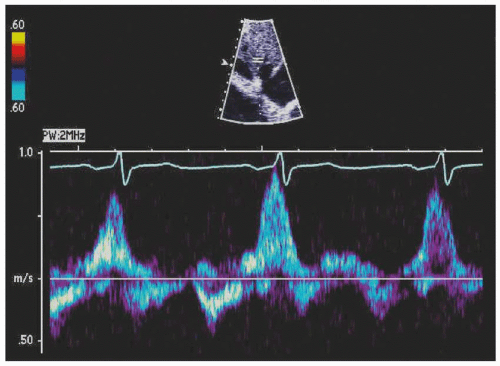

16. Which of the following is compatible with the hepatic venous flow in Figure 28-2?

16. Answer: D. The hepatic venous flow shows a large Ar signal compatible with normal RA systolic function in the presence of increased RVEDP. In early stages of RV diastolic dysfunction, RVEDP is increased, whereas mean RAP is normal. This hemodynamic finding is compatible with option D. Systemic congestion occurs with increased RA mean pressure and predominant forward diastolic flow in all other choices.